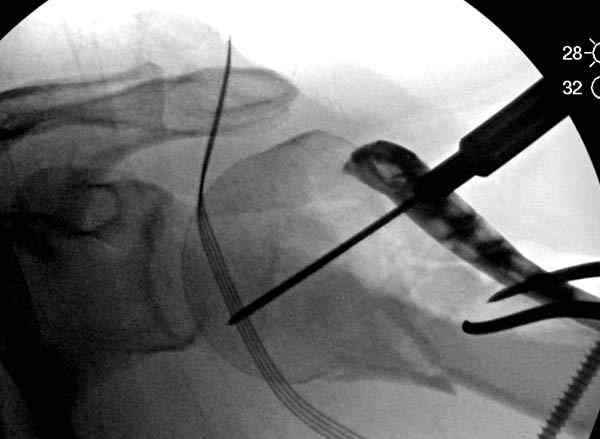

Рентгенограммы действительно с дефектом укладки, но интраоперационная репозиция, можете поверить, была удовлетворительная как в акcиальной, так и в сагиттальной плоскостях. Интраоперационная рентгенограмма прилагается, хотя укладка тоже на ахти. По тактике - разделяю Ваше мнение об отсутствии необходимости реостеосинтеза, а тем более об эндопротезировании, хотя это все было предложено пациентке ведущими ортопедами-травматологами России.

Для облегчения рентгенологического контроля во время операции мы применяем полусидячее, так называемое положение “beach chair” на операционном столе. Наши столы позволяют поднять ножной конец до необходимой высоты, только надо усадить больного к ножному концу стола.

Ошибки встречаются тогда, когда удовлетворяются только одной проекцией рентгена.

Здесь пример открытой репозиции 57 летнего с переломом плеча (1,2) смещение обнаружено на интероперационном снимке. При нормальной прямой проекция (3) угловое смещение обнаружили в аксиальной проекции (4)

После устранения смещения пластина установлена выше (5,6,7) и финальные снимки (8,9,10)